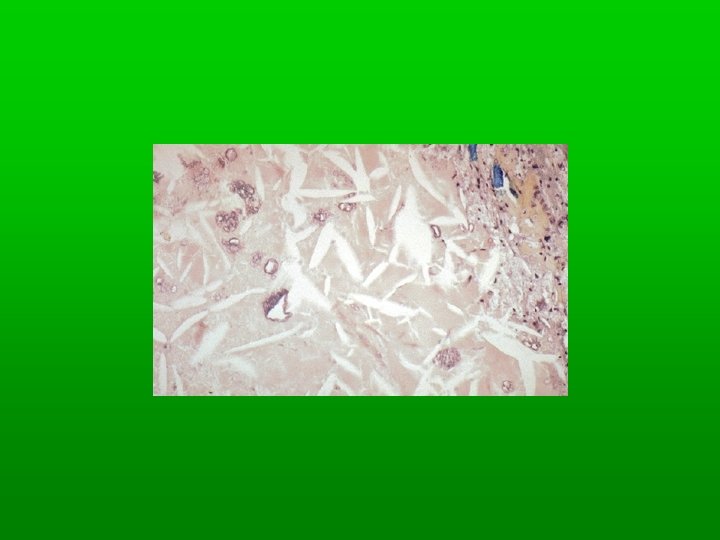

Light of microscopy fatty change Early: small fat vacuoles in the cytoplasm around the nucleus. Later stages: the vacuoles coalesce to create cleared spaces that displace the nucleus to the cell periphery Occasionally contiguous cells rupture (fatty cysts)